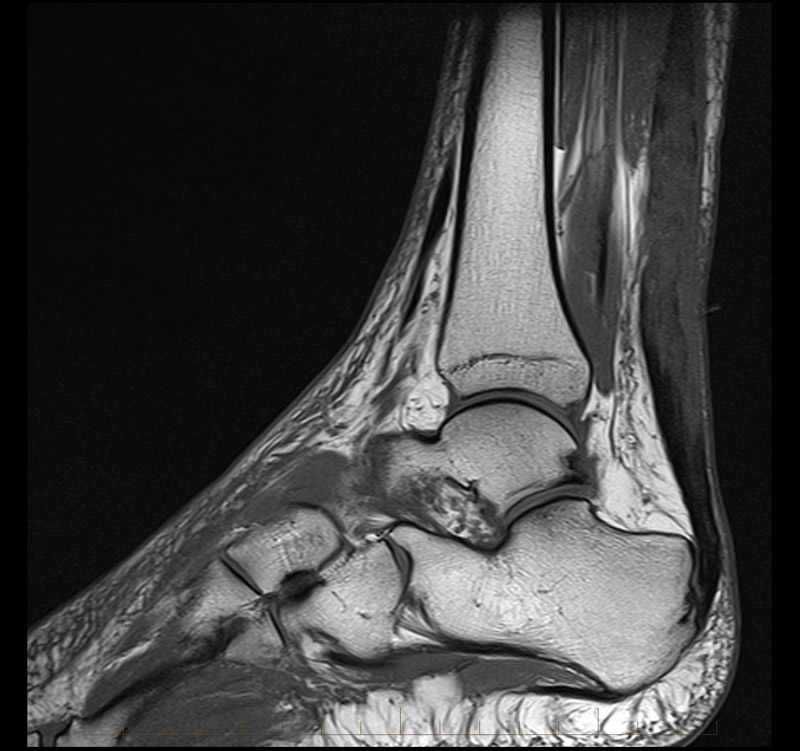

MRI Achilles Tendon – Melbourne Radiology

Achilles Tendon Pathology – Radsource

MRI Achilles Tendon – Melbourne Radiology

MRI Achilles Tendon – Melbourne Radiology